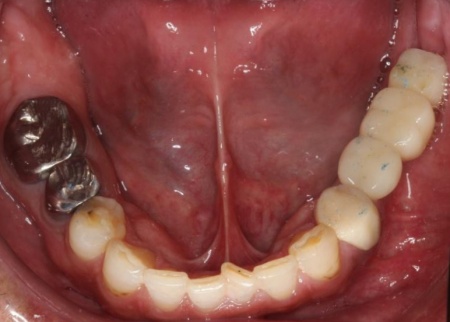

他院で治療を行った左下奥歯3本のインプラントは、土台をそのまま活かして人工歯だけ作り直し、噛み合わせを調整します。

左下奥歯1本、右下奥歯2本に装着されていた古い被せ物はすべて外し、ジルコニアクラウンと交換しました。

左上奥歯は、装着されていた金属の古い詰め物を外し、白い樹脂を直接詰める「ダイレクトボンディング」で修復しました。